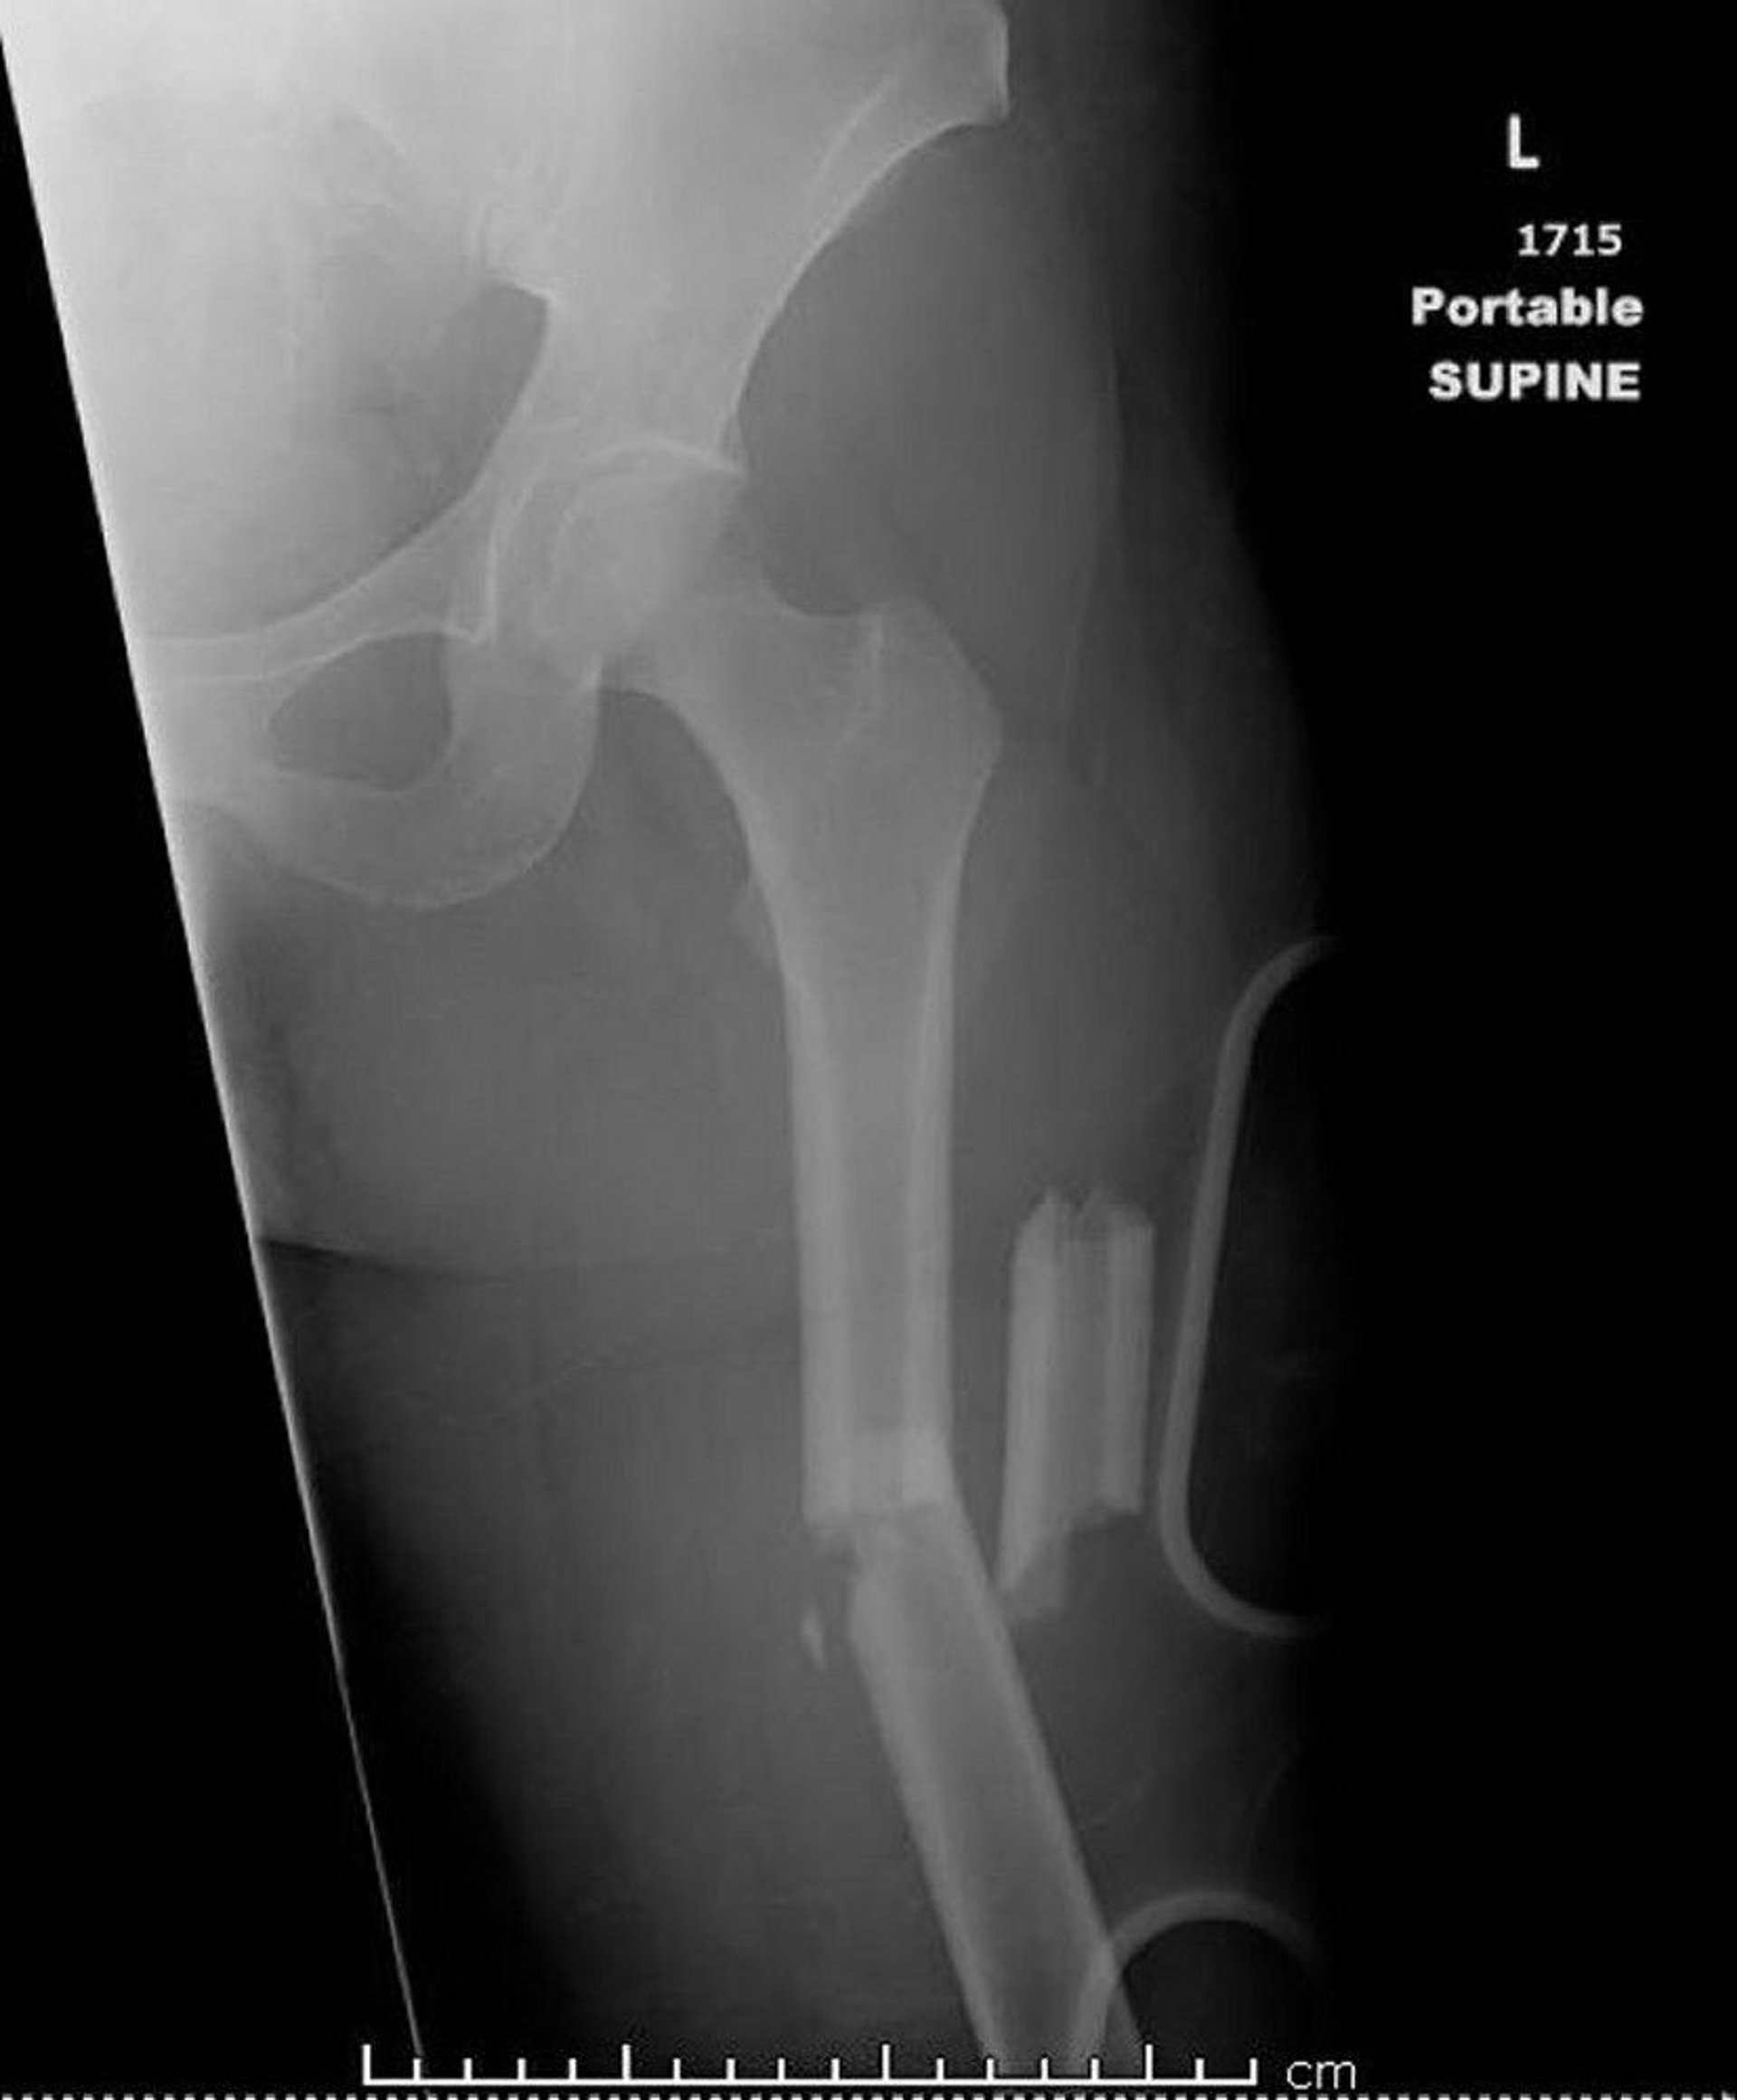

Midshaft Thighbone Fracture

This image shows a femur that is fractured in more than two places (comminuted).

Image courtesy of Danielle Campagne, MD.